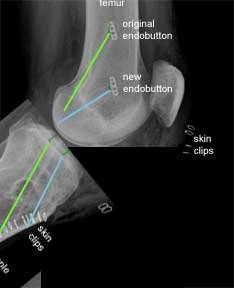

This is an X-ray, of the same patient, taken from the side instead of the front. The green lines show the original tunnels and the blue lines the new tunnels.

For the femoral tunnels the higher endobutton is from the original procedure and the lower endobutton is from the revision procedure.

The new tibial tunnel (blue) is more anterior (closer to the front) than the original tunnel. This is a more anatomic position for the tibial insertion of the native ACL.

To further help you to appreciate the differences between the two procedures, I have used a software programme to 'bend' the knee in the X-ray. This shows that the older trans-tibial procedure leads to parallel femoral and tibial tunnels. This is in contrast to the angled tunnels achieved using the ‘more anatomic’ approach.